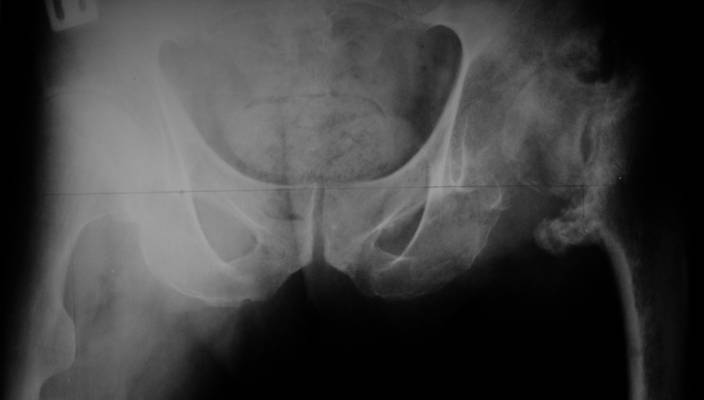

[Ortho] несросшаяся шейка бедра

До травмы проблем с ногой не было. Укорочения, болей и т.п. не

отмечал. Сегодня перемерял укорочение - меньше 7 см намерять не

получается :)

По уровню малых вертелов (с учетом рентгеновского увеличения) получается 5 см.

Клинически ногу низвести путем тракции невозможно. Из движений -

сгибание до 40*, остальные движения  "символические".

Имя     : pelvis.jpg

Url     : http://weborto.net:8080/pipermail/ortho/attachments/20070530/d5d32c11/attachment-0003.jpg